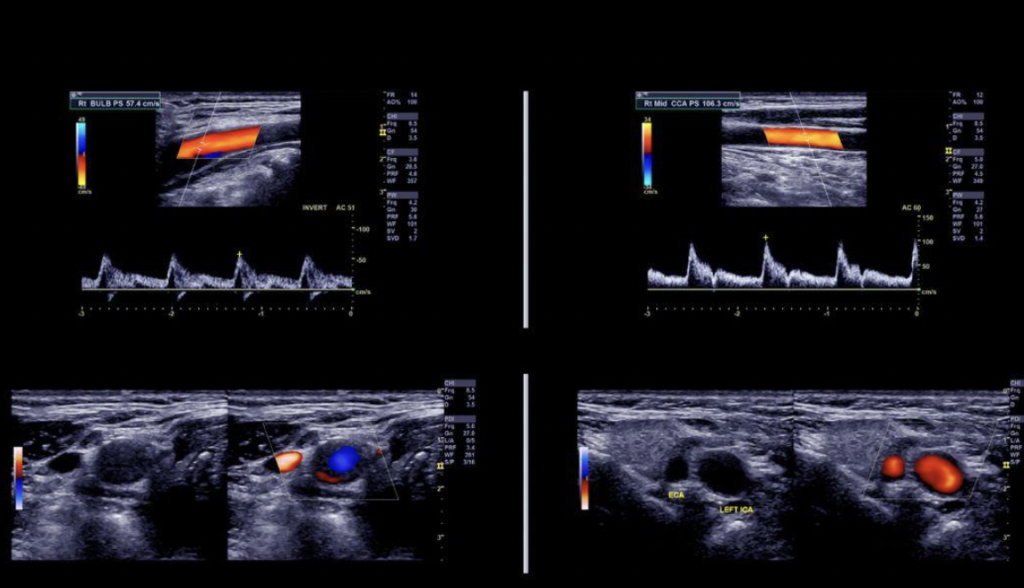

Hapat e ekzaminimit: Përgatitja: Pacienti sht...